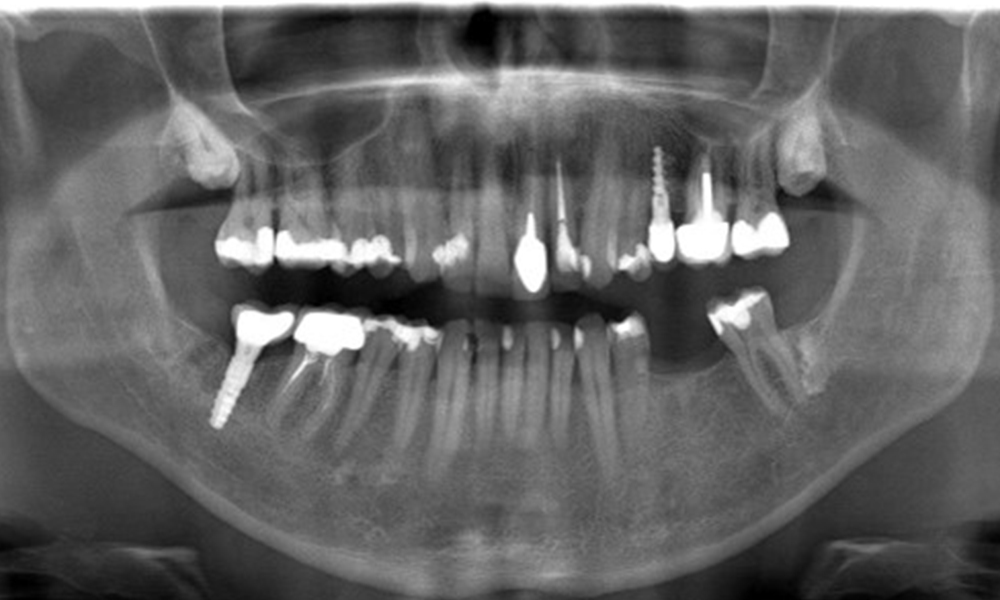

В медицинската история 55-годишният пациент заявява, че няма хронични заболявания и не приема никакви лекарства. Начинът на живот на пациента също е без забележки. Пациентът има няколко зъбни възстановявания и два импланта (2-ри и 4-ти квадрант). Въз основа на настоящите данни се установява гингивит при иначе стабилно пародонтално състояние върху редуцирания пародонт (стадий III, степен А).

Предишни лечения: зъбни възстановявания (съчетание от нескъпоценни метали и керамика), два импланта (2-ри, 4-ти квадрант)

Пациентът не показва особени рискови фактори със специфични дентални последици. Следователно ключовият фактор е изискването по отношение на оралното здраве. В това отношение доброто орално здраве се проявява при стабилен, редуциран пародонт. Ако при контролен преглед се установят данни за увеличаване на дълбочината при сондиране в сравнение с изходното ниво, съчетано с дифузно кървене, следва да се предприеме диагностика с помощта на рентгенова снимка (дентален рентген), за да се установи загуба на периимплантатна кост на ранен етап и да се предприемат съответните интервенции.